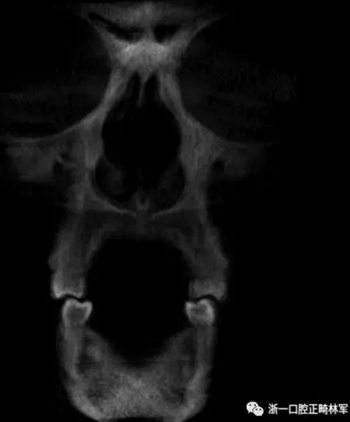

然而,CBCT成像也具有較大的限制:有限的分辨率,牙體組織的不準(zhǔn)確表現(xiàn),以及當(dāng)患者在咬合位或者完全牙尖交錯位CBCT掃描時,上頜骨和下頜骨牙齒之間發(fā)生的混合(圖1)。 這種混合使上頜骨與下頜骨牙齒的自動分離復(fù)雜化,并且由于咬合解剖結(jié)構(gòu)和細(xì)節(jié)的不準(zhǔn)確而使人工分離變得困難。

圖1. 在CBCT中咬合時上頜牙齒和下頜牙齒咬合面的混合和咬合細(xì)節(jié)的喪失。